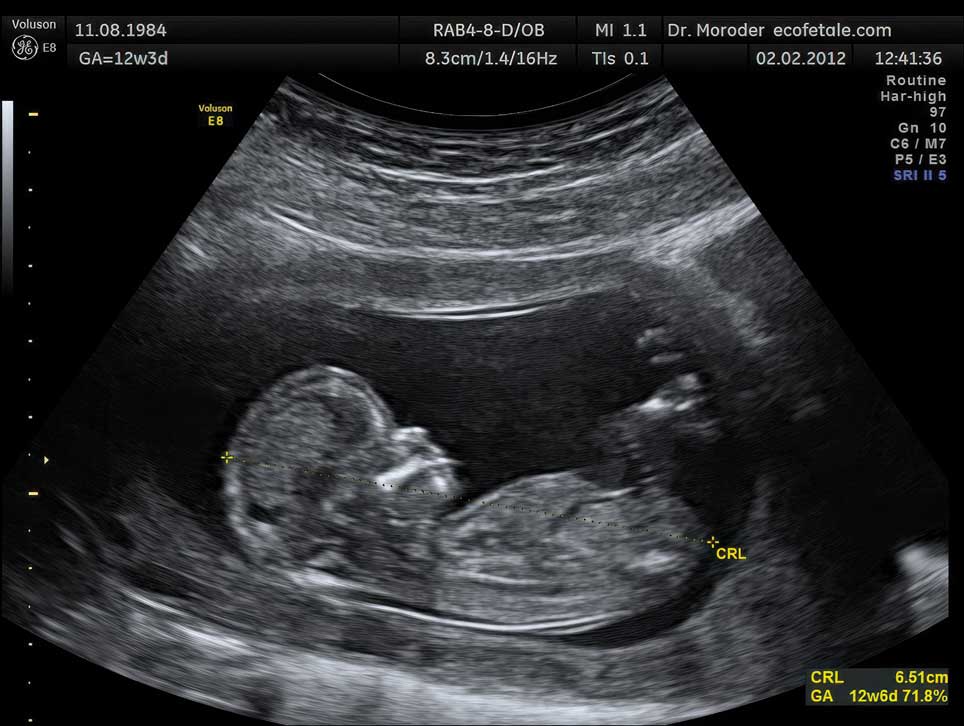

The first film of a living human fetus was made in January 1933 by Davenport Hooker, an anatomist at the University of Pittsburgh. We now consider it natural to observe the fetus in its home environment, but ultrasound technologies are fairly young. Used originally to detect welding flaws in pipes, ultrasonography was first used to image a fetus in the late 1950s by Ian Donald, an obstetrician in Glasgow. Real-time ultrasound scans have been around for only about 50 years, since the 1970s.

Wolfgang Moroder / Wikimedia Commons

Hooker and Humphrey found that very young embryos could not move until 7.5 weeks, when lightly stroking the upper lip, lower lip, or wings of the nostrils—collectively called the perioral area—caused it to sharply move its head and trunk away from the offending strand of hair. The rest of its body still lacked sensation. Between 8 and 9.5 weeks, the fetus had feeling in its lower jaw area, the sides of its mouth, and its nose. By 10.5 to 11 weeks, the upper regions of its face, such as the eyelids, could feel touch. Two or three days after that, at around 11.5 weeks, the entire face of the fetus was sensitive to touch. In that same week, the fetus moved its lower jaw for the first time. At 12 to 12.5 weeks, the fetus had mature reflexes—it closed its lips when Hooker stroked them (in contrast to moving its whole upper body). By 13.5 to 14.5 weeks of age, the fetus was opening and closing its mouth, scrunching its face into a scowl-like expression, moving its tongue, and even swallowing.